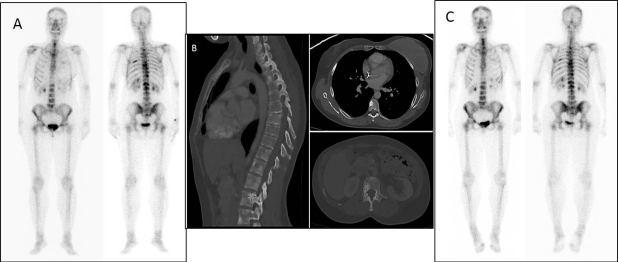

Mujer de 39 años, diagnosticada en 2013 de carcinoma ductal de mama izquierda, con afectación de 23 ganglios axilares. Receptores hormonales positivos (estrógeno 90%, progesterona 15%), CERB-B2 negativo, EGFR negativo, Ki 67 5%. Se realizó GO de estadificación inicial (fig. 1-A), en la que se detectó afectación metastásica ósea múltiple comprometiendo la casi totalidad de la columna vertebral de predominio dorsal, parrilla costal izquierda, esternón, sacro y ambos huesos ilíacos. Se realizó mastectomía radical izquierda y linfadenectomía ipsilateral y se administraron 8 ciclos de quimioterapia (Paclitaxel + Adriamicina + Bevacizumab + Zolendronato) y radioterapia locorregional. Posteriormente, tras anexectomía bilateral laparoscópica profiláctica, continuó tratamiento con Tamoxifeno y ácido zoledrónico.

Se realizó TC de control que mostró extensa afectación ósea, con presencia de lesiones osteoblásticas en cuerpos vertebrales y elementos posteriores lumbares y dorsales, sacro, ambos huesos ilíacos y algunos arcos costales. Se continuó tratamiento con Tamoxifeno y control anual mediante TC durante los 5 años subsiguientes, mostrando persistencia de extensa afectación metastásica ósea, densamente esclerosa, principalmente en columna vertebral y parrilla costal (fig. 1-B). La paciente permaneció estable clínica y analíticamente (fosfatasa alcalina 54U/L, CA-15-3 y CEA dentro de los parámetros de normalidad), sin datos que hicieran sospechar recaída tumoral.

En febrero de 2019, ante la aparición de discreto dolor en cadera derecha y leve aumento del marcador tumoral CA-15-3 (35 U/mL) sospechosos de recaída, se realizó nueva GO que mostró persistencia de lesiones intensamente blásticas a predomino en columna vertebral, sin cambios respecto al estudio realizado 6 años antes (fig. 1-C). Se decidió realizar tomografia por emisión de positrones/TC con fluor-18-desoxi-D-glucosa (18F-FDG-PET/TC) para la caracterización de las lesiones invariables o detectar nuevas localizaciones sugerentes de recidiva. El estudio PET/TC (fig. 2B) demostró la presencia de una nueva lesión ósea intensamente hipermetabólica (SUVmax = 5,35) en región acetabular derecha, sin traducción aparente en la imagen radiológica, muy sugerente de recaída tumoral que justificaba la clínica y la reciente alteración analítica, mientras que el resto de las lesiones basalmente esclerosas e intensamente positivas en la GO resultaban completamente negativas desde el punto de vista metabólico (fig. 2A).